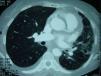

Entre las exploraciones complementarias, en el hemigrama figuraban hemoglobina de 10mg/dl, conteo de leucocitos de 6.620/μl, conteo de plaquetas de 614.000/μl, fibrinógeno de 628mg/dl, velocidad de sedimentación de 86mm/h, proteína C reactiva de 118mg/dl y factor reumatoide de 8,5U/ml (positivo); el resto de los estudios inmunológicos fueron normales. Entre los marcadores tumorales, el CA-125 fue de 43U/ml. En la bioquímica presentaba una función hepática alterada, con alanino-aminotransferasa (GOT) de 126U/l, aspartato-aminotransferasa (GPT) de 85U/l, gammaglutamil transpeptidasa (GGT) de 67U/l y lactatodeshidrogenasa (LDH) de 607U/l. En las pruebas funcionales respiratorias presentaba capacidad vital forzada (FVC) de 2,22l (77%), volumen espirado en el primer segundo (FEV1) de 1,36l (55%), FEV1/FVC del 60% y saturación de oxígeno basal del 90%. No se hallaron alteraciones significativas en la broncoscopia, con citología de broncoaspirado y lavado broncoalveolar negativa y sin otros hallazgos microbiológicos. En la radiografía de tórax vimos una pérdida de volumen del hemotórax izquierdo, con un patrón en vidrio deslustrado y zonas de patrón intersticial, que se verificaron en la TC de alta resolución, con derrame pleural bilateral pequeño, signos de hipertensión pulmonar, disminución de volumen del hemotórax izquierdo con afectación pulmonar difusa, engrosamientos septales interlobulillares e intralobulillares, infiltrado nodular en el lóbulo superior izquierdo más engrosamiento pleural, con enfisema centrolobulillar (fig. 1). En el ecocardiograma se vio una endocarditis aórtica con insuficiencia aórtica muy grave, hipertensión pulmonar ligera-moderada secundaria a elevación de presiones telediastólicas en el ventrículo izquierdo y una fracción de eyección del 50%. Se intervino a la paciente, con mejoría radiológica al alta.

Tomografía computarizada (TC) de alta resolución al ingreso: disminución de volumen del hemotórax izquierdo con afectación pulmonar difusa, engrosamientos septales interlobulillares e intralobulillares, infiltrado nodular en el lóbulo superior izquierdo más engrosamiento pleural, con enfisema centrolobulillar.